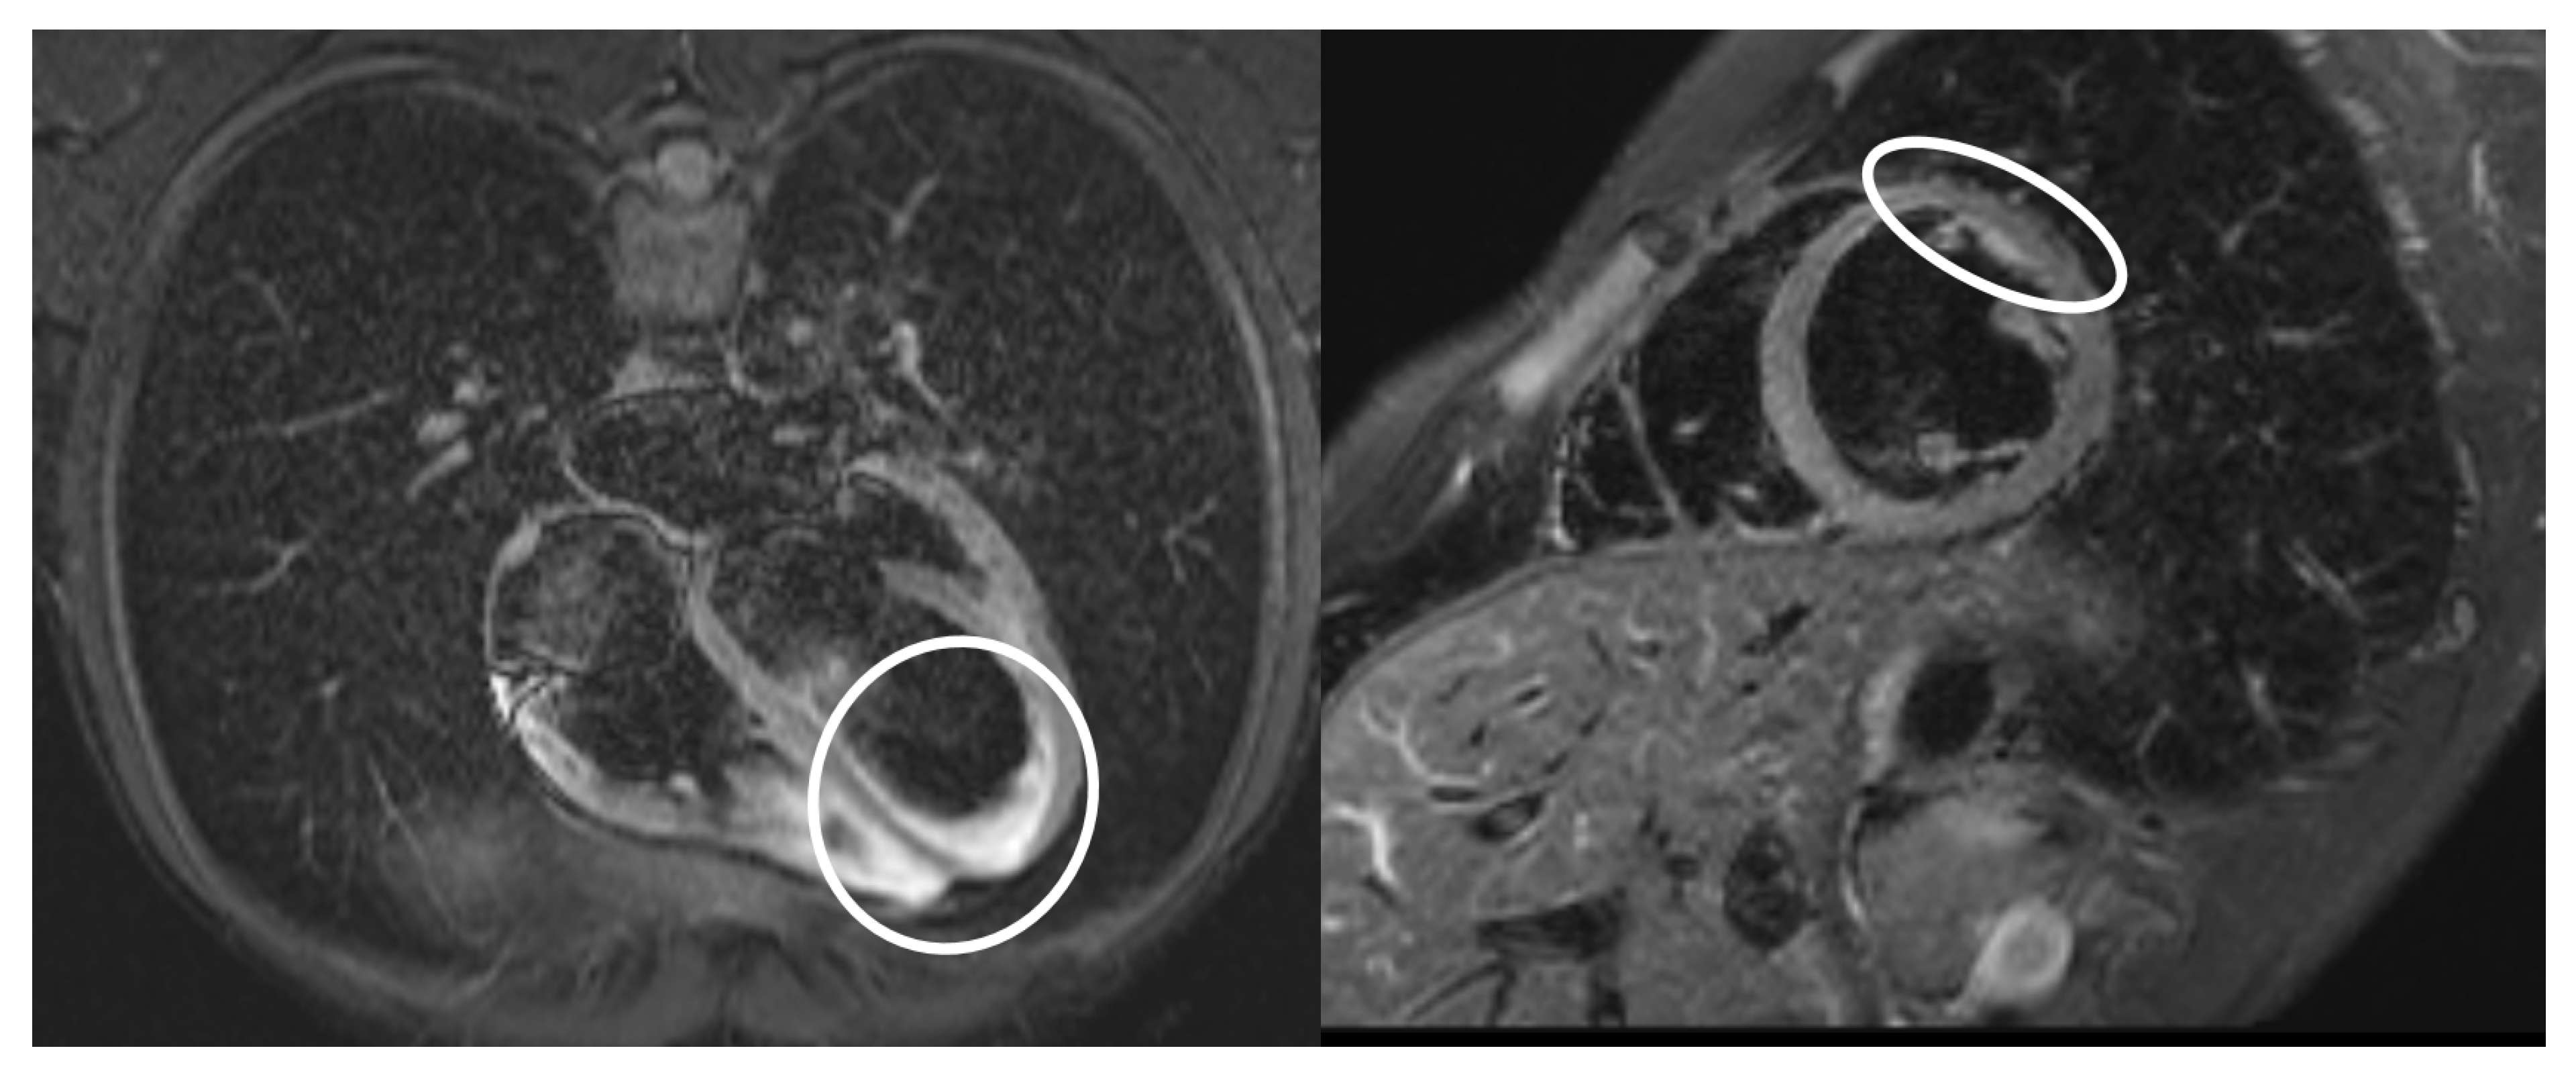

| Echocardiographic evidence of cardiac involvement or physical sigmata of heart failure | Pericardial effusion |